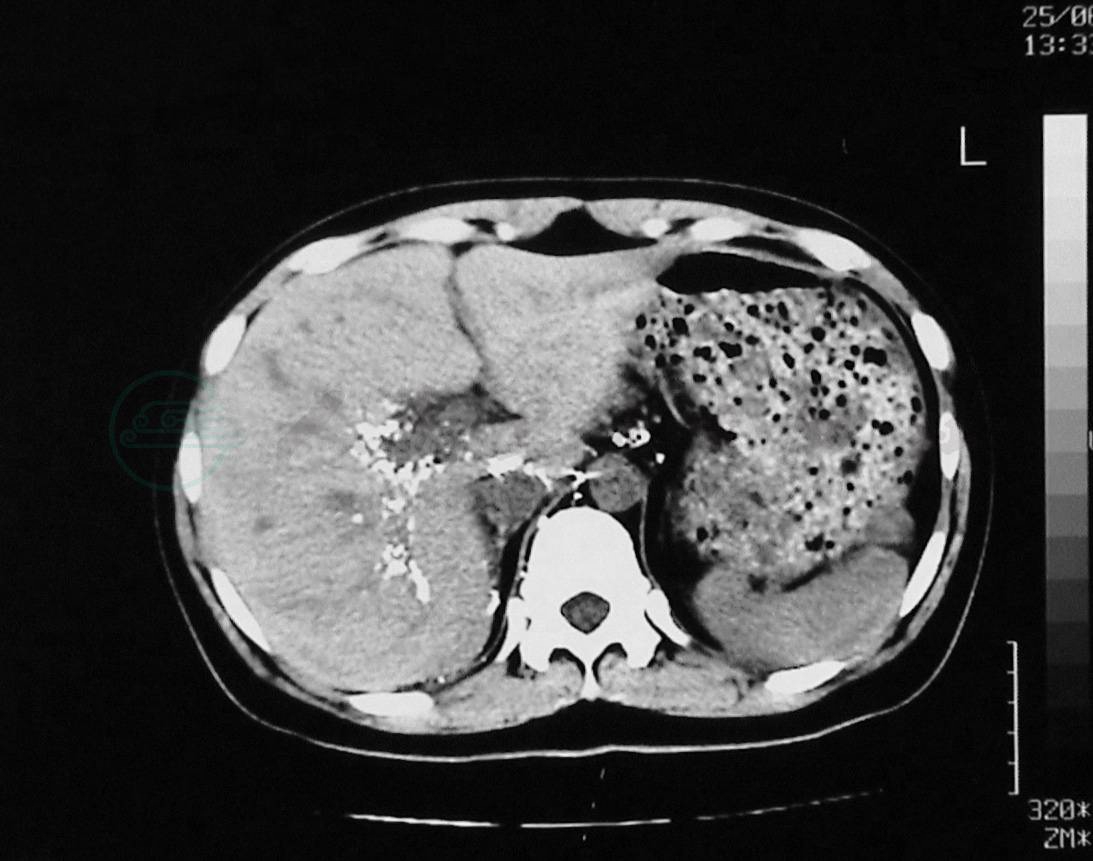

(2) 腹膜后淋巴管反流加重,进一步造成腹膜后脏器的乳糜反流如肝脏乳糜反流(图12)、胰腺乳糜反流(图13)、脾的乳糜反流、肾乳糜反流、子宫阴道乳糜反流等。值得注意的是:脏器的乳糜反流并不意味着该脏器乳糜漏的发生。

图12LCT显示碘油反流进入肝脏

图13LCT显示碘油反流进入胰腺